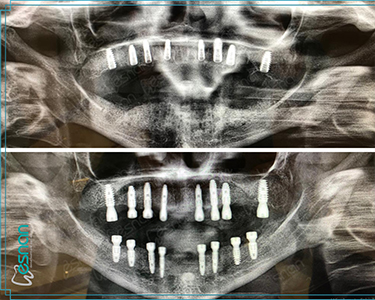

Oral, dental, and maxillofacial radiology is a crucial element in comprehensive dental care. It utilizes various imaging techniques, such as periapical radiographs, panoramic radiographs, cone beam computed tomography (CBCT), and occlusal radiographs. These tools provide valuable insights into the underlying structures of the mouth, teeth, and jaws, allowing dentists to diagnose and treat a wide range of conditions, including dental caries, periodontal disease, infections, tumors, and developmental abnormalities. Early detection and accurate diagnosis through oral, dental, and maxillofacial radiology can significantly impact treatment outcomes and improve overall oral health.

Planning for dental implants

Each examination listed above serves a specific purpose in dental diagnostics. Panoramic X-rays provide a broad view of your teeth, jaws, and surrounding structures, while intraoral radiography offers detailed images of individual teeth. Cephalometric X-rays assess facial growth and development, and CBCT scans provide detailed 3D images for complex cases like implant planning and oral surgery. Our experienced team is dedicated to utilizing these technologies to deliver precise and personalized care for every patient.